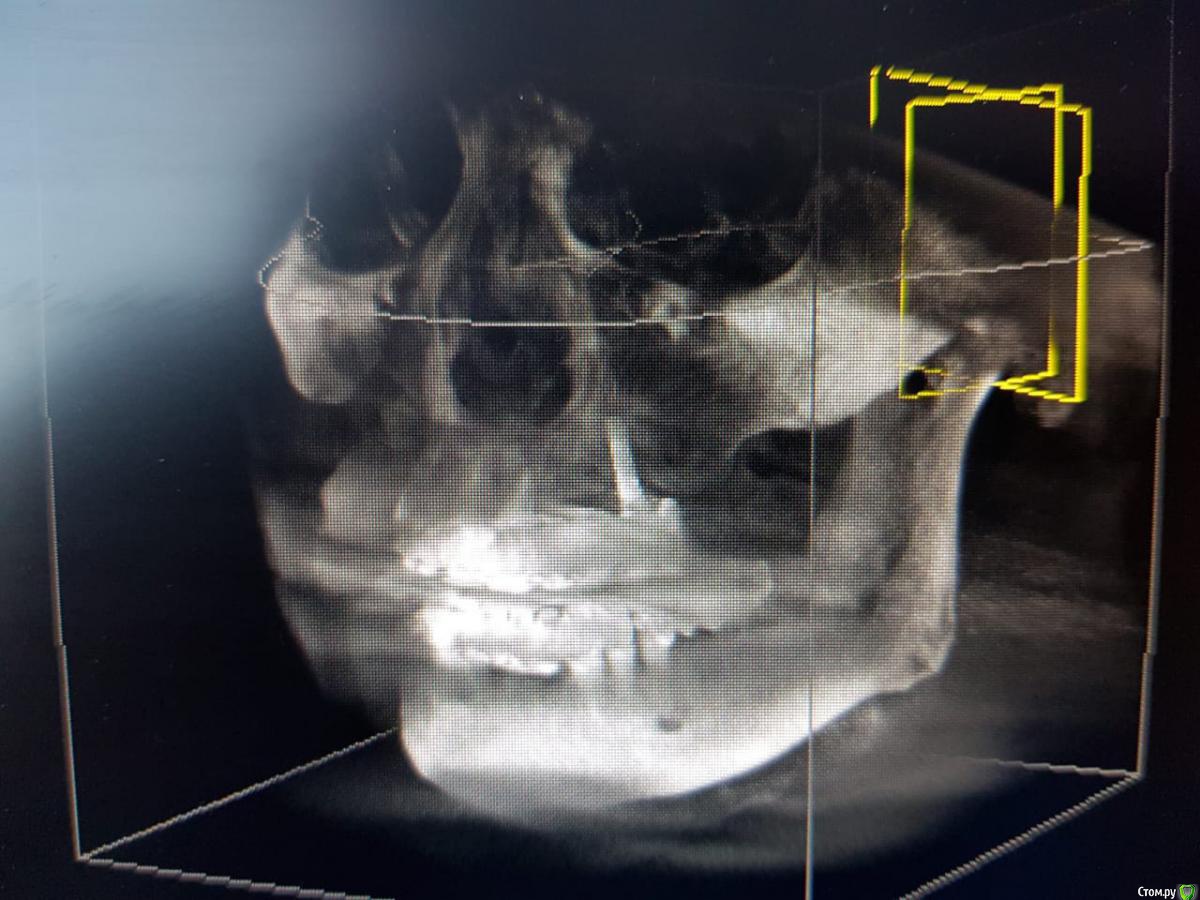

Sunshine Опубликовано 14 марта, 2019 Поделиться Опубликовано 14 марта, 2019 Уважаемые, врачи!Моему отцу 2,5 года назад установили импланты (в другом регионе), и сделали мост, "зацепившись" за живой зуб и имплант...Его ничего не беспокоило до недавнего времени. Теперь вся эта конструкция начала ходить ходуном ... приносит ему боль, естественно полноценно кушать не может.Обратившись в стоматологию по новому месту жительства, стоматологи сообщили, что так делать нельзя ни при каких обстоятельствах, и что надо все снимать, оставшиеся зубы удалять, ждать пока рассосется образовавшаяся киста в районе существующего импланта, и устанавливать новые импланты. Соответственно, вопрос. Так как отец в пенсионном возрасте, то крайне боится вообще остаться без зубов, для него это трагедия. Какие существуют варианты развития событий в нашей ситуации в "щадящем" режиме, но чтобы было все грамотно и четко сделано, дабы больше не возвращаться к вопросу зубов на верхнем ряду. p.s врач который устанавливал данную конструкцию сказал чтоб приезжали-он все поправит, но я его уже не отпускаю, потому что думаю это снова на пару лет...а дальше только хуже... Ссылка на комментарий

kramer Опубликовано 14 марта, 2019 Поделиться Опубликовано 14 марта, 2019 Если нужен несъемный протез, тогда надо удалять все зубы и прежний имплантат, одномоментно ставить 4-6-8 имплантатов (надо более детально изучать случай), временный несъмный протез в день операции или через несколько дней. Ссылка на комментарий

kramer Опубликовано 14 марта, 2019 Поделиться Опубликовано 14 марта, 2019 а что возможно сделать, не прибегая к удалению оставшихся зубов? Имеет ли смысл оставлять их? Какие последствия? Зубы верхней челюсти несостоятельны, сохранить нельзя Если на время удаления всей конструкции ставить съемный протез(это я так понимаю снимаются на ночь и в стаканчик? )), то это же только на то время пока не приживутся новые имплантаты? (примерно 3-6 месяцев) Временный протез несъемный, прикручивается в день операции или через несколько дней (при условии, что первичная стабильность имплантатов хорошая. Если нет, тогда как по сценарию, который вы написали) и что с кистой? Удаляется вместе с имплантатом Ссылка на комментарий